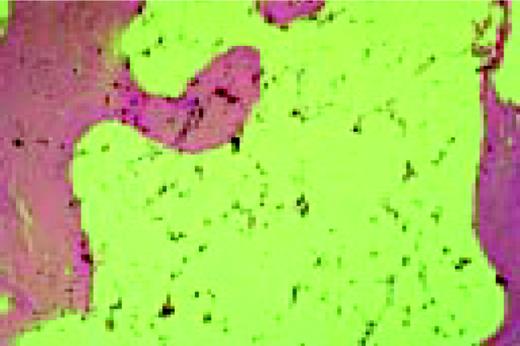

Slide E8

Agnogenic myeloid metaplasia with myelofibrosis. This low-power bone marrow biopsy clearly shows the fibrosis associated with this disease. This H&E-stained preparation shows virtual replacement of the marrow cavity with light pink-staining fibrotic tissue.FIG104